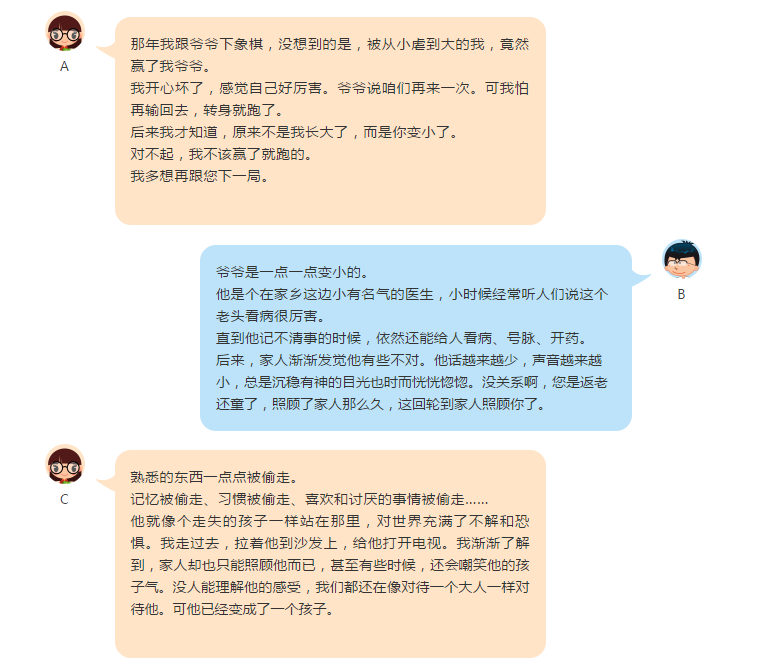

患上老年痴呆症,对家人的打击也是巨大的。

像被倒转过来的沙漏,眼看着她一点点漏掉过去,熟悉干练的她越来越少,笨拙陌生的她越来越多,不知哪一天哪一刻会失去她,多想再和清醒的她说几句,哪怕她再唠叨也无所谓。我觉得爱很重要,特别是在她的晚年,即使做错了什么,也别训斥,别大声和她说话,给她夸奖和笑容,让她感受到你们的爱。

无法想象在中国有多少家庭正在承受着老年痴呆症带来的折磨。

生活中有许多你不得不去面对的事,这就是责任。有时候会想,责任这东西是不是上天留给世人的一种考验,有人逃匿了,也有人承受了。